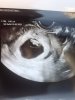

Hej już po wizycie. 8+0, bąbel ma już 1,66cm, serduszko 168/min ❤️ I już ma raczki i nóżki, słodko sobie macha 🤪 Na zdjęciu nie widać za bardzo kończyn, ale na szczęście wszystko w porządku. A miałam jakieś złe przeczucia niepotrzebnie 🤦🏼‍♀️

• image.jpg

1,4 MB · Wyświetleń: 130